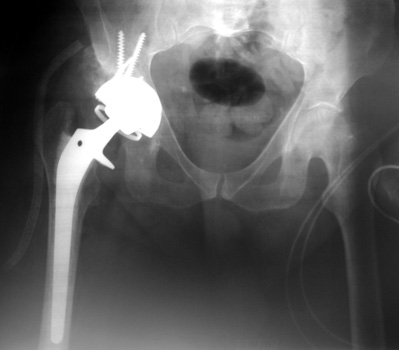

Dislocated femoral component secondary to steep acetabular cup inclination, pre and post revision. Note constraining ring about femoral head, which helps maintain head in cup